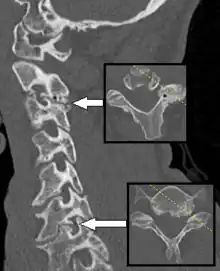

Axial skeleton and extremities

For the axial skeleton and extremities, CT is often used to image complex fractures, especially ones around joints, because of its ability to reconstruct the area of interest in multiple planes. Fractures, ligamentous injuries, and dislocations can easily be recognized with a 0.2 mm resolution.[71][72] With modern dual-energy CT scanners, new areas of use have been established, such as aiding in the diagnosis of gout.[73]

Multiplanar reconstruction (MPR) is the process of converting data from one anatomical plane (usually transverse) to other planes. It can be used for thin slices as well as projections. Multiplanar reconstruction is possible as present CT scanners provide almost isotropic resolution.[108]

MPR is used almost in every scan. The spine is frequently examined with it.[109] An image of the spine in axial plane can only show one vertebral bone at a time and cannot show its relation with other vertebral bones. By reformatting the data in other planes, visualization of the relative position can be achieved in sagittal and coronal plane.[110]

New software allows the reconstruction of data in non-orthogonal (oblique) planes, which help in the visualization of organs which are not in orthogonal planes.[111][112] It is better suited for visualization of the anatomical structure of the bronchi as they do not lie orthogonal to the direction of the scan.[113]